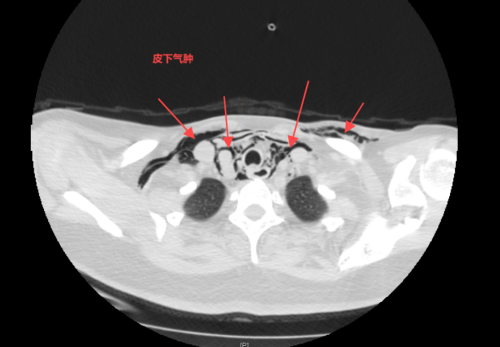

接诊的急诊科副主任、主任医师赫留党详细询问了她的经历,完善体查,发现李小华颈部及胸壁局部肿胀,考虑吞食异物导致食管破裂的可能,立马陪同患者完善了颈部及胸部CT,结果证实了之前的判断,影像学提示颈段食管异物,并气管、食管局部破裂,颈部皮下、纵膈及前胸部多发气肿。